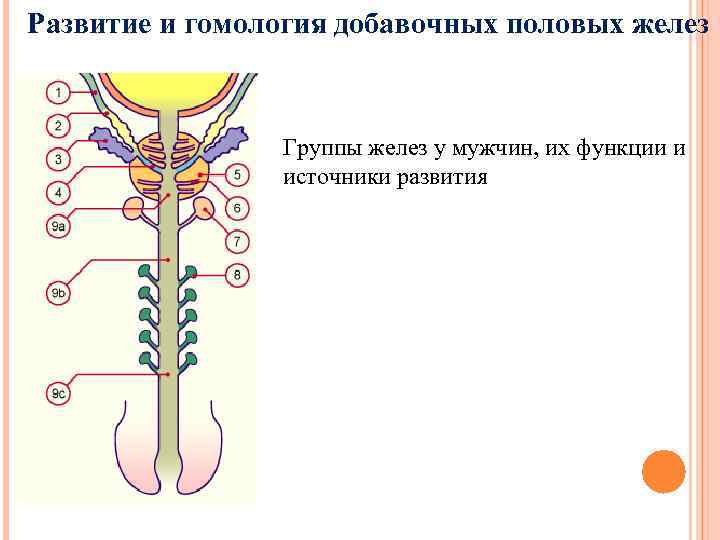

Развитие и гомология добавочных половых желез Группы желез у мужчин, их функции и источники развития

Развитие и гомология добавочных половых желез Группы желез у мужчин, их функции и источники развития